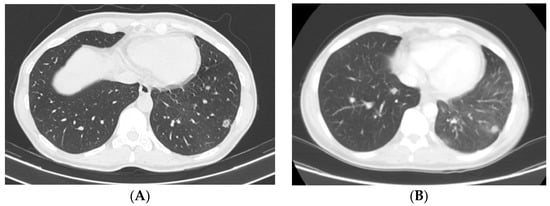

Clinical Scenario